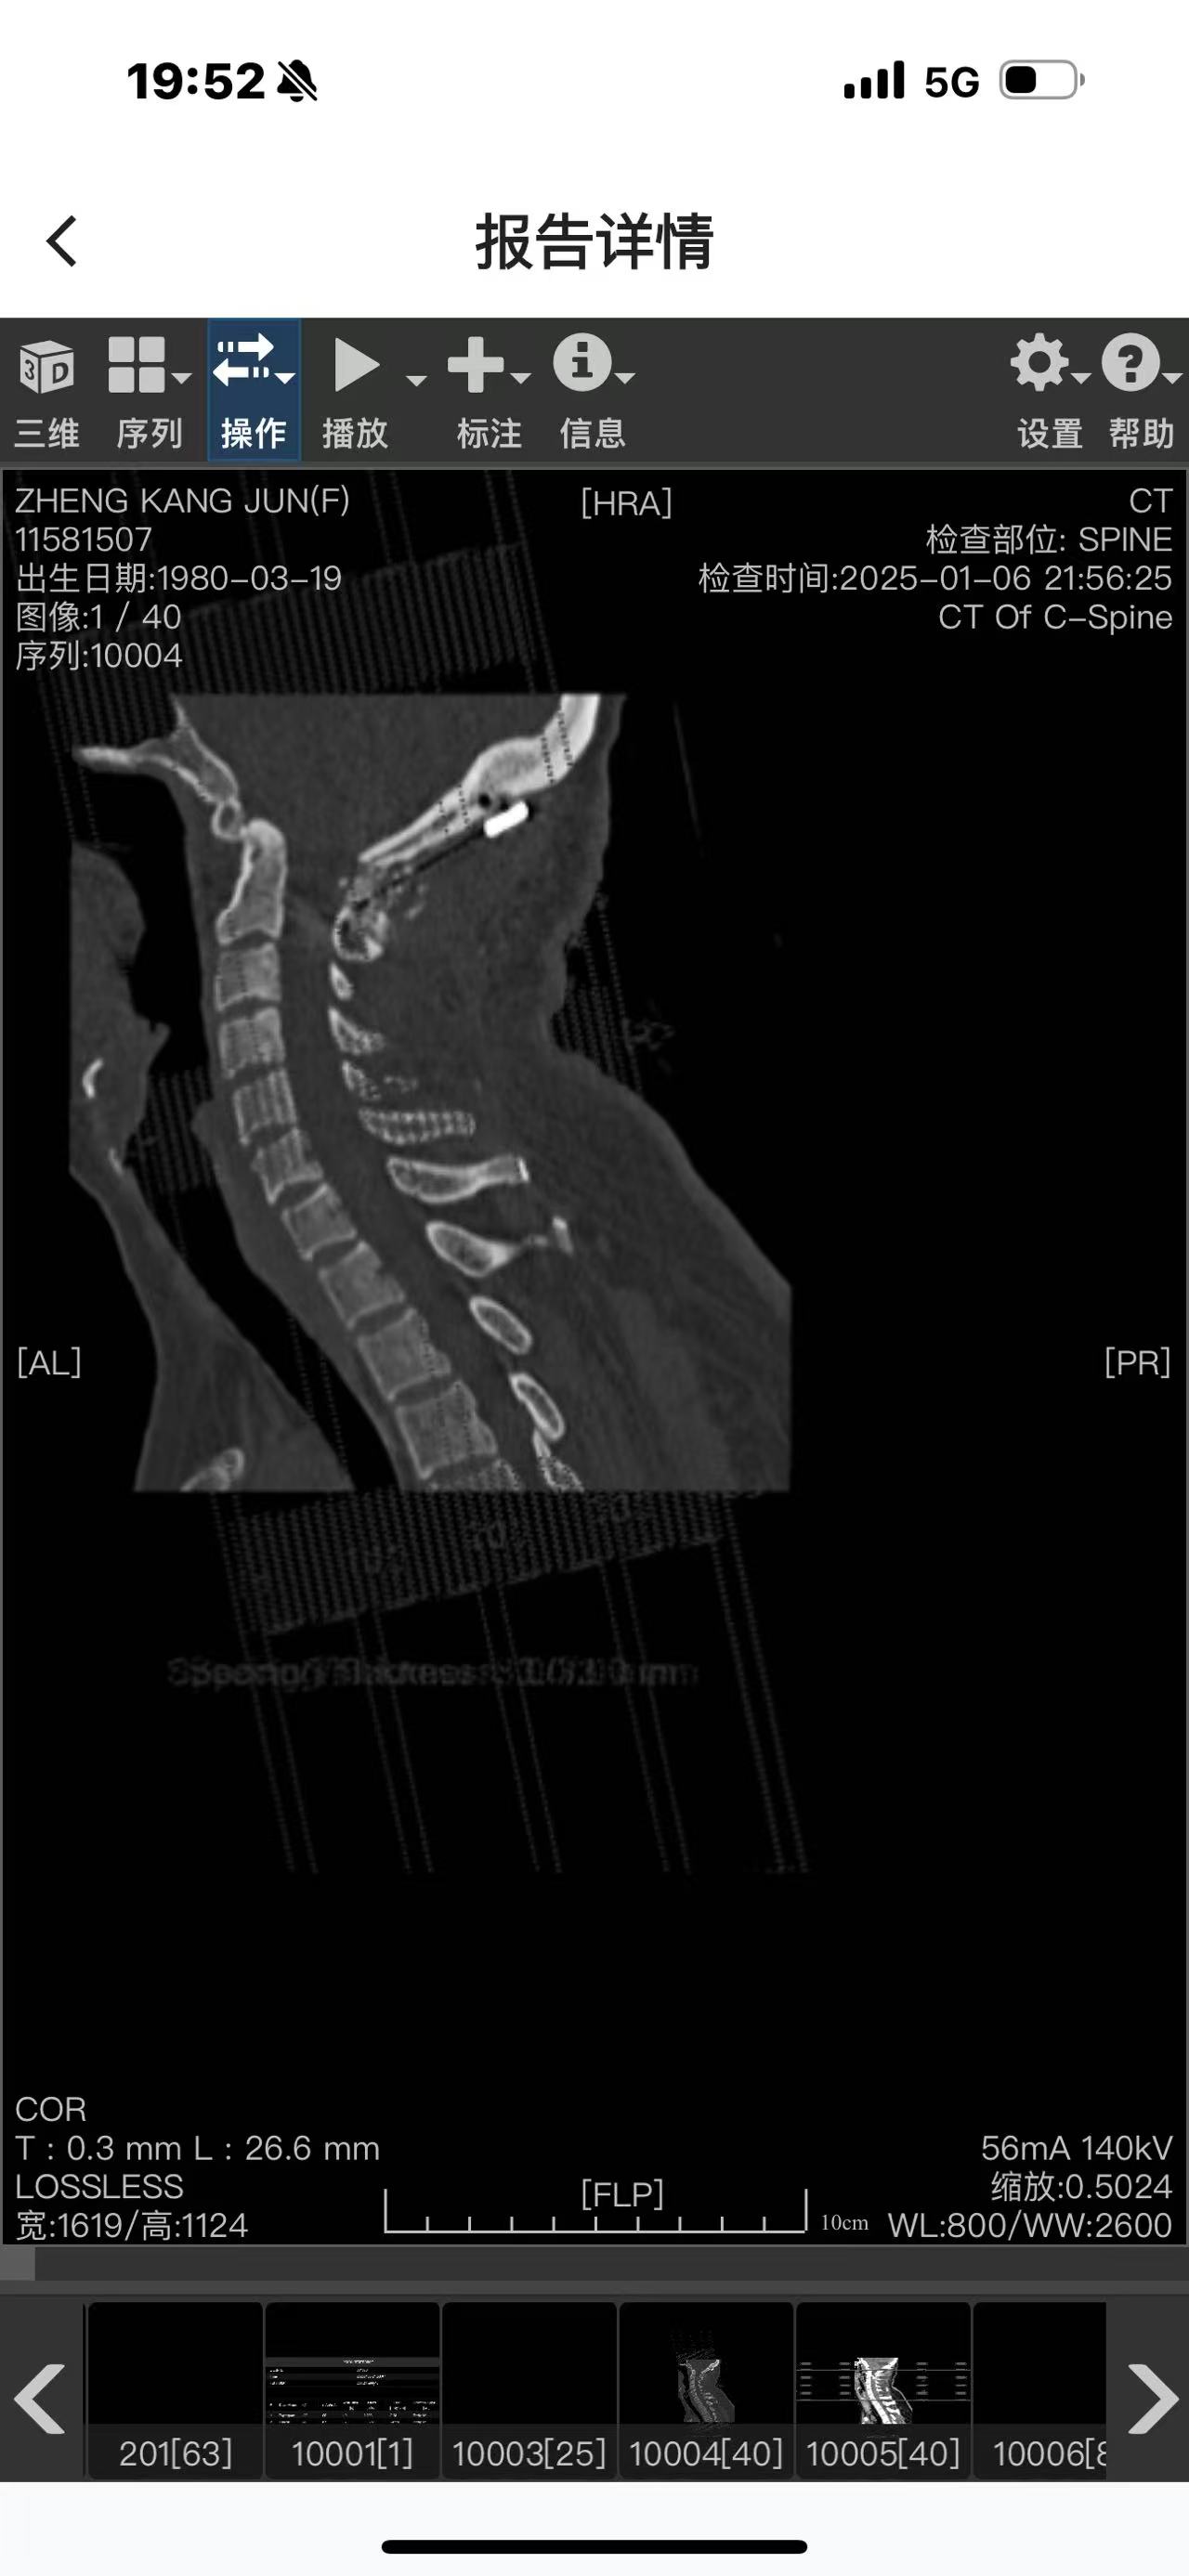

• 诊断:寰枢椎脱位

• 术后影像: